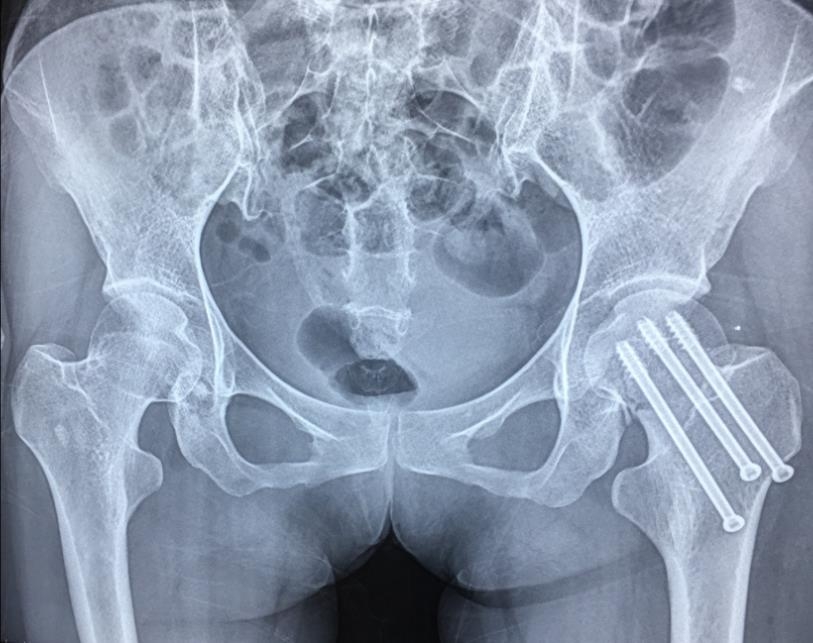

2、复位标准:C-B透视

正位:Shenton's线恢复;恢复股骨颈135°以上的颈干角,大粗隆尖端与股头中心在同一平面;骨折断端阳性支撑。

2、标准放置螺钉为倒三角形,其中下方螺钉在股骨矩,后方螺钉在后方骨皮质、研究发现倒三角形平行三枚螺钉能提供最佳的固定强度;

空心钉固定的三原则:“贴边、平行、倒品”

1、贴边是指3枚螺钉在股骨颈内,尽量靠近外围皮质。这样3枚螺钉作为一个整体,对整个骨折面可形成面状加压,如果3枚螺钉不够离散,更趋于点状加压,稳定性较差,不能较好地对抗扭转和剪切。

图1 3枚螺钉在股骨颈内的理想位置